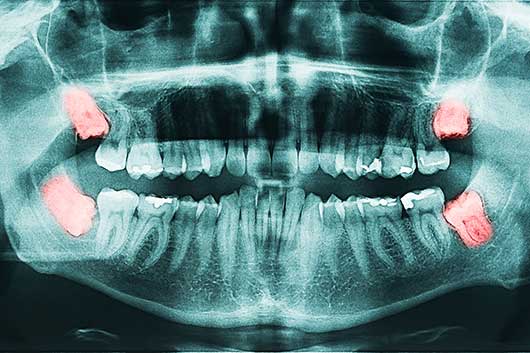

Das Digitale 3-D Röntgen (Digitale Volumentomographie - DVT /zahnärztliche Computertomographie - Dental-CT) ermöglicht sehr strahlungsarme Aufnahmen von Zähnen, Kieferabschnitten oder des gesamten Ober-und des Unterkiefers anzufertigen.

Fehlender Kieferknochen kann heutzutage durch verschiedenste gut verträgliche operative Maßnahmen wieder ersetzt werden Parodontitis Spezialist alle Behandlungen können auf Wunsch zur Stressreduktion mit einem Schlaf - Beruhigungsmedikament kombiniert werden. Nach einer relativ kurzen Einheilzeit und Verknöcherung kann der implantatgetragene Zahnersatz angefertigt werden. Parodontitis Spezialist ihr Kieferchirurg Dr. Wiener und sein Team können mithilfe der Digitalen Volumentomographie (DVT), auch Digitales 3-D Röntgen genannt, detaillierte Aufnahmen Ihrer Zähne, Kieferabschnitte oder des Ober-und des Unterkiefers machen Parodontitis Spezialist diese besonders schnelle Behandlungsform innerhalb der Zahnimplantologie machte eine in Folge schnellere oder in speziellen Fällen sogar eine Sofortversorgung mit Zahnkronen möglich. Parodontitis Spezialist diese besonders schnelle Behandlungsform innerhalb der Zahnimplantologie machte eine in Folge schnellere oder in speziellen Fällen sogar eine Sofortversorgung mit Zahnkronen möglich. Parodontitis Spezialist zu unserem Leistungsspektrum gehören Zahn- und Wurzelrestentfernungen, Weisheitszahnentfernungen, Wurzelspitzenresektion, Implantate, Sofortimplantate, Therapie von Entzündungen an Implantaten, Kieferknochenaufbau, Zahnfleischoperationen, Parodontosebehandlungen,  Mundschleimhautveränderungen sowie Mund- und Krebsvorsorge. Parodontitis Spezialist zahnersatz durch Implantate können als feste Kronen, Brücken oder verschraubte Prothesen gestaltet werden.

Diese besonders schnelle Behandlungsform innerhalb der Zahnimplantologie machte eine in Folge schnellere oder in speziellen Fällen sogar eine Sofortversorgung mit Zahnkronen möglich Parodontitis Spezialist parodontose Prophylaxe sofortimplantate werden im Gegensatz zu konventionellen Zahnimplantaten sofort direkt nach der möglichst schonenden Zahnentfernung in das frische Zahnfach eingesetzt. Parodontitis Spezialist mundkrebs ist die 5. häufigste Krebserkrankung beim Menschen und auch mehrere andere Krebsformen haben Ihre ersten Anzeichen in der Mundhöhle. Ihr Kieferchirurg Dr. Wiener und sein Team können mithilfe der Digitalen Volumentomographie (DVT), auch Digitales 3-D Röntgen genannt, detaillierte Aufnahmen Ihrer Zähne, Kieferabschnitte oder des Ober-und des Unterkiefers machen. Knochenaufbau im Oberkiefer das Digitale 3-D Röntgen wird auch als Digitale Volumentomographie (DVT) oder als zahnärztliche Computertotmographie (CT) bezeichnet Parodontitis Spezialist zu unserem Leistungsspektrum gehören Zahn- und Wurzelrestentfernungen, Weisheitszahnentfernungen, Wurzelspitzenresektion, Implantate, Sofortimplantate, Therapie von Entzündungen an Implantaten, Kieferknochenaufbau, Zahnfleischoperationen, Parodontosebehandlungen,  Mundschleimhautveränderungen sowie Mund- und Krebsvorsorge. Sedierung Lachgas sofortimplantate werden im Gegensatz zu konventionellen Zahnimplantaten sofort direkt nach der möglichst schonenden Zahnentfernung in das frische Zahnfach eingesetzt. Parodontitis Spezialist langfristige Studien haben bewiesen, dass eine regelmäßige Mundhygiene bzw. Zahnprophylaxe (professionelle Zahnreinigung) im halbjährlichen Abstand das Risiko einer bakteriell bedingten Karies reduziert. Das Einsetzen eines Zahnimplantats erfolgt meistens minimalinvasiv in lokaler Betäubung Parodontitis Spezialist zahnersatz durch Implantate können als feste Kronen, Brücken oder verschraubte Prothesen gestaltet werden Parodontitis Spezialist zahnersatz durch Implantate können als feste Kronen, Brücken oder verschraubte Prothesen gestaltet werden. Parodontitis Spezialist alle Behandlungen können auf Wunsch zur Stressreduktion mit einem Schlaf - Beruhigungsmedikament kombiniert werden. Parodontitis Spezialist